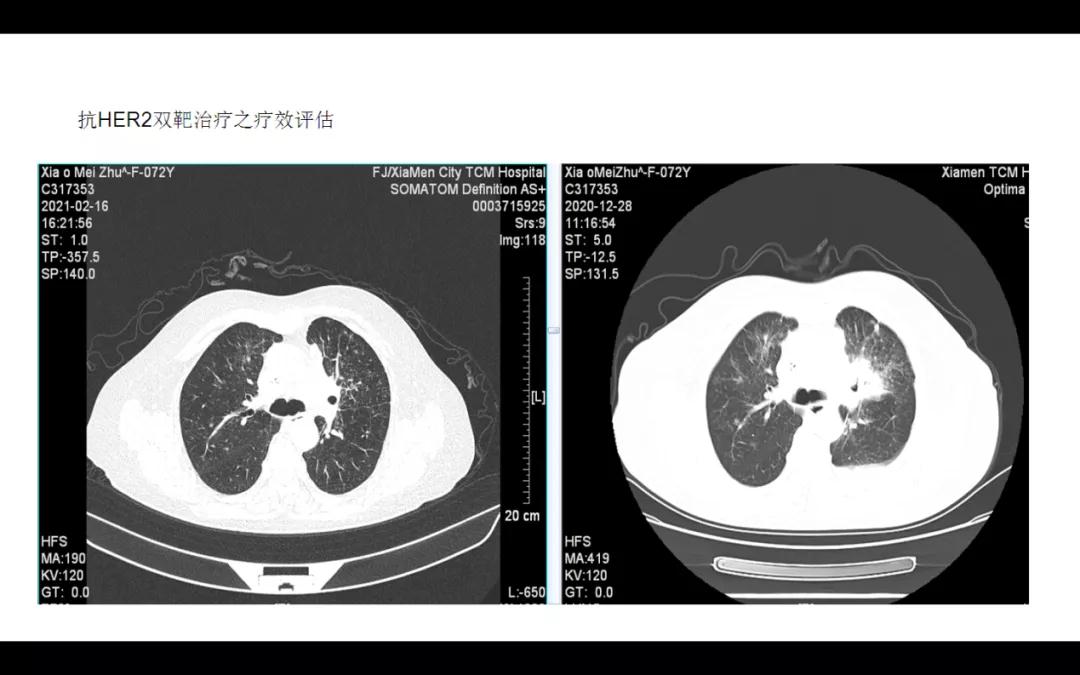

因总体疗效评估为部分进展(PD),2020-11-12及2020-12-08改行“曲妥珠单抗+培美曲塞”共两周期,疗效评估仍为进展(PD);2021-01-03、2021-01-25、2021-02-16、2021-03-11、2021-04-01、2021-04-21、2021-05-12、2021-06-02、2021-06-23、2021-07-14及2021-08-04改行“曲妥珠单抗330mg ivgtt d1+吡咯替尼320mg po d1-21,q3W”靶向治疗共十一周期,并于2021-03-12起间断予“地舒单抗”抗骨转移治疗,过程顺利,第一周期治疗后咳嗽症状缓解,用药期间偶有腹泻(为黄色稀糊便,日三四行),两周期联合靶向治疗后影像学复查疗效评估为部分缓解(PR)。

本例患者为初诊Ⅳ期肺腺癌(左胸膜转移),历经七线抗肿瘤治疗总生存期已达57个月(接近5年),其中末线“曲妥珠单抗330mg ivgtt d1+吡咯替尼320mg po d1-21,q3W”双靶联合治疗共十一周期(PFS 8个月),期间病灶一度缩小。